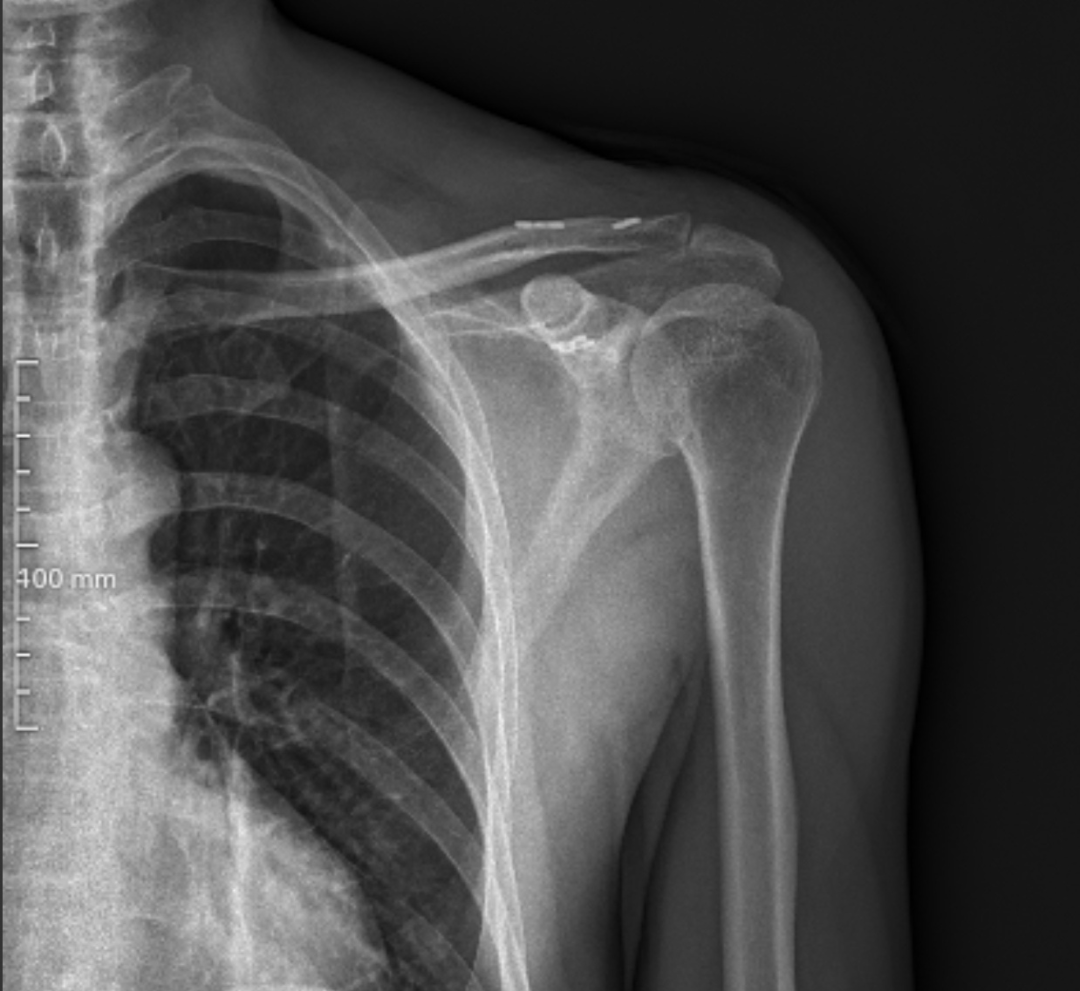

患者刘先生因“摔伤致左肩关节疼痛、活动受限19小时”入院,查体可见左锁骨远端明显突起、压痛,肩关节活动受限。结合影像学检查,确诊为左侧肩锁关节脱位(Rockwood III型),传统保守治疗难以恢复关节稳定性,手术治疗是最佳选择。

手术过程顺利,术中精准复位脱位关节,骨道位置精准且仅有3毫米,完美重建韧带结构。术后X线片显示肩锁关节解剖复位满意,内固定位置良好,患者疼痛明显缓解,肩关节功能逐步恢复。